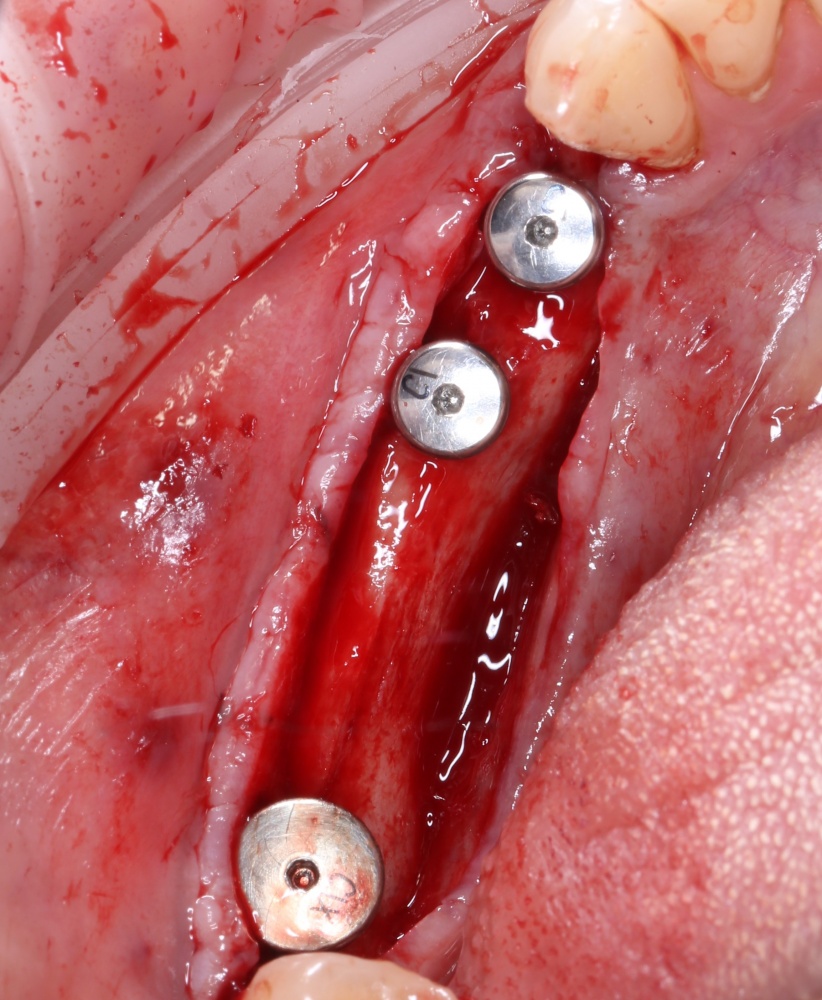

Вернемся к нашему клиническому случаю. Мы уже поставили импланты с расчетом на будущую высоту альвеолярного гребня и положение будущих зубов:

И, если в предыдущей части мы рассматривали ситуацию, когда принимающее ложе имеет относительно простой рельеф, и у нас не возникло сложностей с адаптацией аутоблока, то в случае, рассматриваемом сегодня, нормальная и точная адаптация крупного костного фрагмента, практически, невозможна. Именно поэтому мы решили использовать направленную костную регенерацию (НКР), поскольку с адаптацией тестообразного по консистенции графта проблем, обычно, никогда не бывает. Как, например, в этом случае: